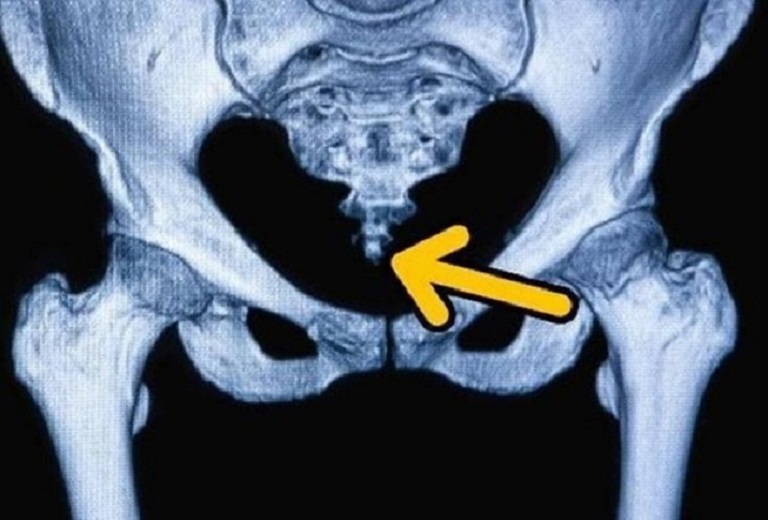

Đau xương cụt (Coccydynia hoặc Tailbone Pain) xảy ra do xương cụt bị mất ổn định dẫn đến viêm các khớp lân cận (đặc biệt là khớp cùng chậu). Cơn đau ở xương cụt sẽ chuyển biến từ nhẹ đến dữ dội và thường tăng nặng khi ngồi xuống, đứng lên hoặc ngả người ra sau khi ngồi trên ghế.

Cơn đau xương cụt có thể lan xuống hông và chân khiến cho việc đi lại gặp khó khăn. Đôi khi, chúng ta có thể cảm thấy nhói đau ở xương cụt khi đi vệ sinh hoặc quan hệ tình dục.